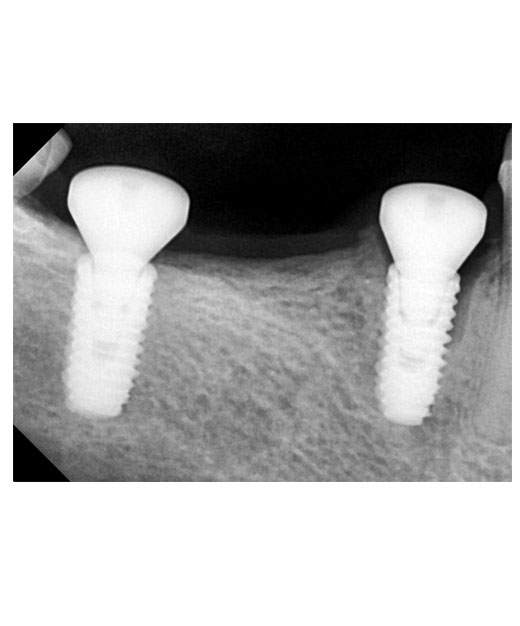

Guided Implant Surgery involves the use of advanced 3D imaging and computer-aided design (CAD) to plan the exact placement of dental implants. This meticulous planning process allows our dental specialists to visualize the patient’s oral anatomy in great detail, ensuring the implants are placed in the most ideal position for both functionality and aesthetics. The procedure is tailored to each patient's unique needs, ensuring a personalized treatment plan.

These technique assures that the implant is precisely placed without any damage to nerves, vessels and wouldn't perforate maxillary sinus too.